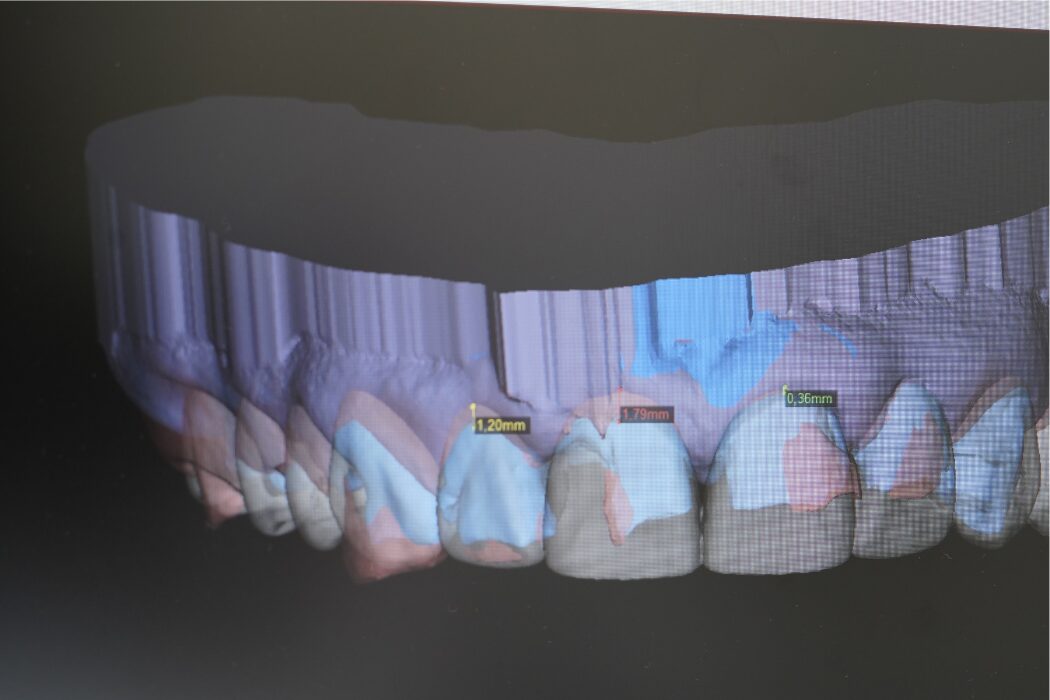

El bruxismo es una de las principales causas del desgaste dental. Detectarlo a tiempo permite evitar sensibilidad, fracturas y pérdida de estructura dental.

El desgaste dental no siempre está relacionado con la edad. Puede provocar sensibilidad, fracturas y cambios en la sonrisa. Detectarlo a tiempo permite proteger los dientes y evitar tratamientos más complejos.